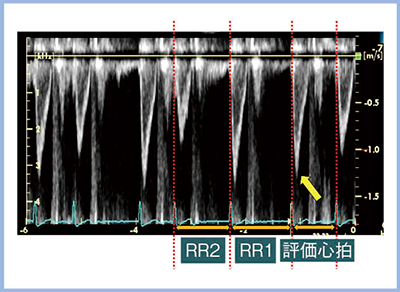

心房細動における心機能評価に当たっては,先行R-R間隔(RR1)と先々行R-R間隔(RR2)の比(RR1/RR2)がほぼ1となる区間を評価心拍としてエコー指標を評価すると,複数心拍で評価した値と良好な相関が得られる(図3)。これが,index beatという考え方であり,index beatを自動で簡便に検出する機能がR-R Navigationである。検出されたindex beatは心電図上,黄色で表示され(図4),その心拍を用いることで,心房細動の心機能評価においても再現性良くエコー指標を計測することができる。また,index beatは自動検出されるため,解析時間の短縮にもつながる。

図3 心房細動における評価心拍の検出